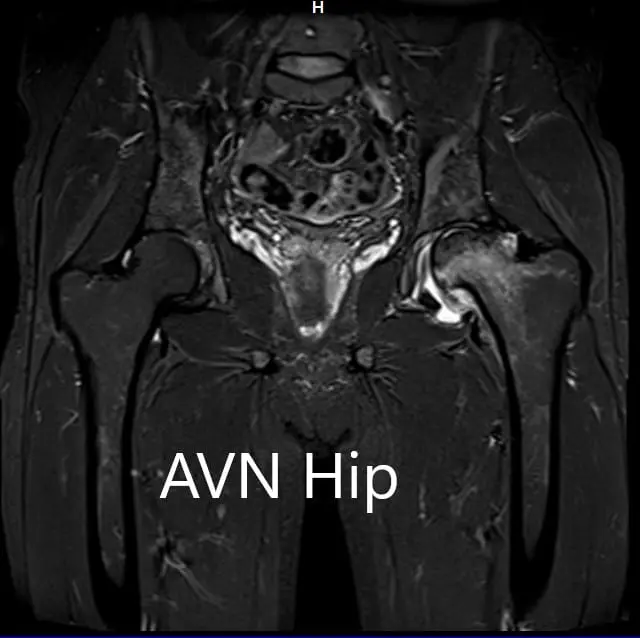

An MRI was obtained for diagnostic confirmation and staging of the disease. The left femoral head was collapsed with irregular contour and showed areas of altered signal intensity with a line of demarcation. Hypointense areas both on T1WI & T2WI seen in head suggestive of sclerosis. Surrounding marrow edema was seen

The left hip had advanced avascular necrosis with a collapse. The right hip was uninvolved presently. He was educated about the worsening collapse of the hip joint leading to his symptoms. Although the patient was young, he was advised a total hip replacement surgery in view of the collapse of the head of the femur with arthritis.